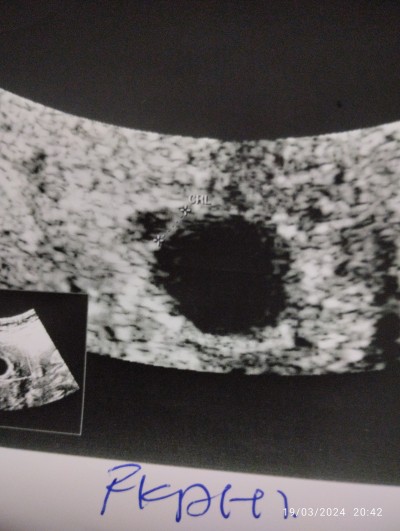

Kesem çokmu büyük ya anlamadım

o yuvarlak olanmi kese yoksa yandakimi bana yardımcı olun lütfen yorum yapin

Gebelik haftası

6

Yuvarlak kesede kesenin içi boş gibi doktor bebeği gördü mü canım

Evet bak sola yapışmış resmen

O buyuk yuvarlak yer kople kese sol yukarida nokta nokta cizgi seklinde gorunende bebis, bebis henuz cok kucuk oldugu icin kesen buyuk gorunuyor :)

Diğer çocuğumda hiç böyle değildi ya

Belki yakinlastirmistir goruntuyu o yuzdende buyuk gorunuyo olabilir

Yok ya büyük bence sol fotrafta uzak hali bile cok büyük büyük olması kötümü acaba